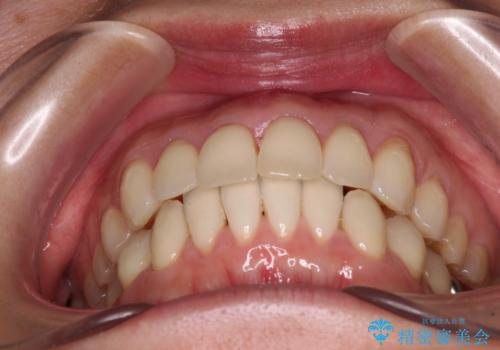

- 上下の前歯のデコボコを気にして来院された患者様です。

妊娠中であり、途中通院が難しくなる可能性があることから、インビザラインによる矯正治療を行うこととしました。

上下顎歯列全体の後方移動とIPR(歯と歯の間を削る)によってデコボコが解消するように設計しました。